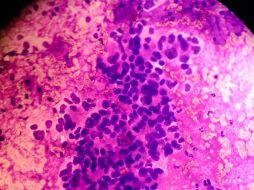

Suplementos ¿Qué es el adenocarcinoma de páncreas? 14 de marzo de 2017 - 20:50 hs Cáncer Enfermedades